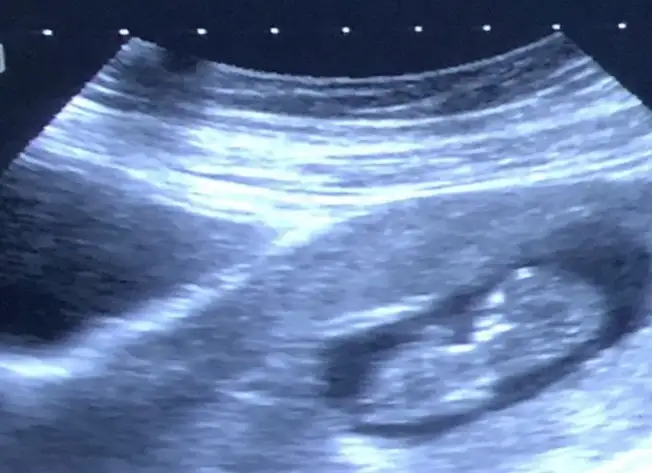

dr soylemeden siz gorun genital nub teorisi ( bebegin cinsiyeti)

13+5 ultrason görüntüsü, bizi de tahmin eder misiniz :)